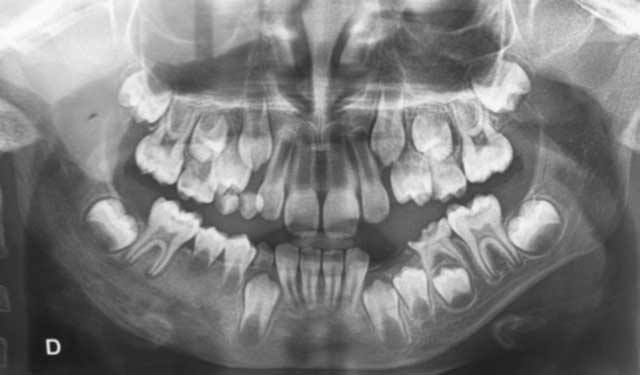

L’examen radiologique a montré une ostéo- condensation mal limitée allant de la 83 à la 85 (Fig.2).

Fig.2 : Examen radiologique montrant une ostéo-condensation au niveau du secteur prémoléro-molaire mandibulaire droit. |

Fig.2 : Examen radiologique montrant une ostéo-condensation au niveau du secteur prémoléro-molaire mandibulaire droit.